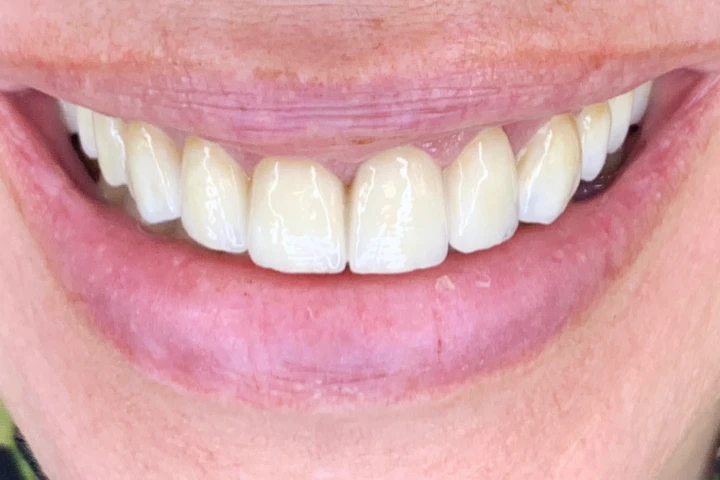

Holivudski osmesi - pre i posle

- Ostvarite svoj san o blistavom izgledu zuba! Galerija radova će vas uveriti da je holivudski osmeh dostupan svima.